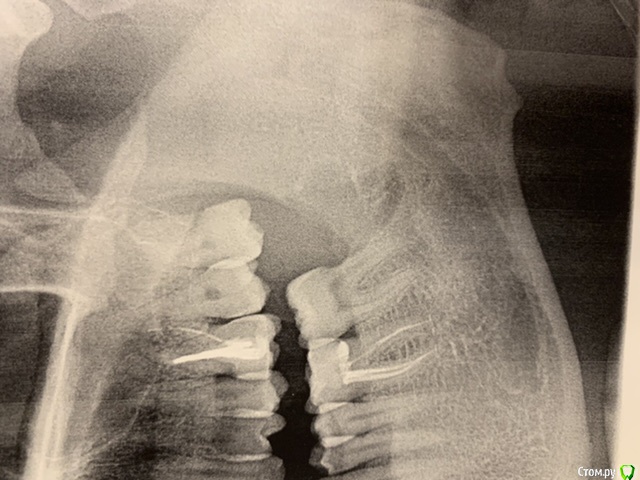

strelokvlz Опубликовано 4 августа, 2020 Поделиться Опубликовано 4 августа, 2020 (изменено) Здравствуйте. 17 июля нагноилась полностью скрытая под десной левая нижняя восьмёрка. Обратился в частную клинику где произвели разрез десны чтобы освободить зуб. Все промыли, назначили антибиотики Ципролет 5 дней и отправили на ОПТГ. Сказали что зуб сложный, удалять не возьмутся и направили в городскую стоматологию. Сделал снимки и пошёл на приём в поликлинику. К слову она неплохая, врачи хорошие. Хирург посмотрел снимок, сказал что есть полость(киста?) на зубе и назначил дату удаления. 24 июля зуб удалили. Резали десну, пилили, но в целом все прошло минут за 20. Десну зашили, поставили дренаж. Выписали амоксицилин 5 дней, антигистаминное, лёд. Повторный приём через 3 дня. Отека не было, боль умеренная в течение двух дней. На следующий день после операции вылетел дренаж во время еды, а ещё через день полностью разошлись швы и появилась боль в десне. На следующий день поехал на приём. Врач осмотрел лунку и сказал что в принципе ничего страшного что швы разошлись, равна большая и мол иногда, но бывает. Промыл антисептиком и плотно уложил альвожель в рану, повторно зашивать не стал. Сказал приезжать через день для замены лекарства. Начиная со следующего дня появилась постоянная ноющая боль и сильное реагирование соседней 7ки на холодное. Ездил 4 раза на замену лекарства и осмотр. Пожаловался на боль, после чего отправили на рентген. По снимку врач сказал что из за травмы оголилась шейка соседнего зуба и предложил либо потерпеть до зарастания Десны либо депульпировать. Но так как семерка здоровая, от депульпации я отказался. Опять заложили альвожель и отправили домой, на повторный приём только через 5 дней. В итоге на 11 день после операции присутствует постоянная ноющая боль в районе лунке, не очень приятный запах, переодически слюна имеет кисло сладкий привкус (гной?) и сильная чувствительность в районе лунки (корень семерки?). Так и должно быть? Или стоит волноваться? Врачу я вроде бы доверяю и с его слов ему нравится как проходит заживление, но я уже устал от постоянной ноющей боли и запаха. Зарастёт ли шейка семерки или лучше все таки согласиться на депульпацию? Снимки оптг до операции и после прикрепляю. Изменено 4 августа, 2020 пользователем strelokvlz Ссылка на комментарий